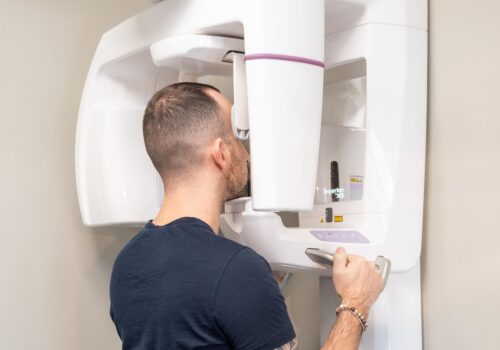

La Dottoressa Stefania Lazzaroni ti illustrerà quale soluzione è perfetta per te, eseguendo una valutazione diagnostica ad hoc con una strumentazione di prim’ordine: Radiografie Endorali , Panoramiche Dentali e Radiologia 2D e 3D.